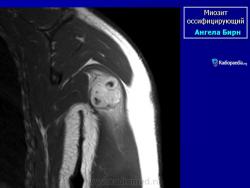

Рентгенологические признаки однотипны для всех форм оссифицирующего миозита; плотный рисунок периферической и менее плотный центральной части повреждения.

При компьютерной томографии визуализируется кальцификация гетеротопической кости, которая продвигается от наружного края образующегося узла в центр.

Рентгенологические признаки однотипны для всех форм оссифицирующего миозита; плотный рисунок периферической и менее плотный центральной части повреждения.